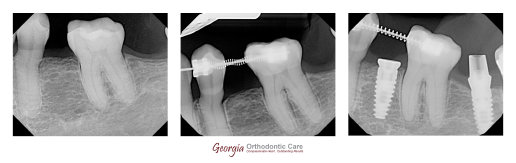

Patient missed #20 & #19 tipped forward . Orthodontic treatment to reopen space for #20 before implant insertion. Photo courtesy of Dr. Lia Vo at the Vo Dentistry.